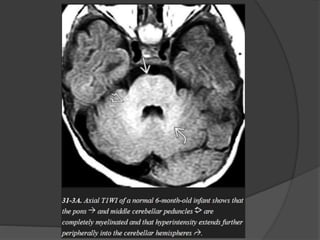

INFRATENTORIAL  Dorsal medulla/ midbrain  Inferior / superior cerebellar peduncles  Middle cerebellar peduncle  Cerebellar white matter T1WI T2WI First appear at Birth Birth Birth Birth 1 mth 3 mth 1 – 3 mth 8 – 18 mth